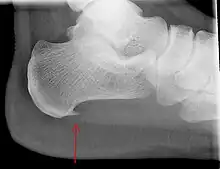

An incidental finding associated with this condition is a heel spur, a small bony calcification on the calcaneus (heel bone), which can be found in up to 50% of those with plantar fasciitis.[6] In such cases, it is the underlying plantar fasciitis that produces the heel pain, and not the spur itself.[13] The condition is responsible for the creation of the spur though the clinical significance of heel spurs in plantar fasciitis remains unclear.[12]

Medical imaging is not routinely needed. It is expensive and does not typically change how plantar fasciitis is managed.[15] When the diagnosis is not clinically apparent, lateral view X-rays of the ankle are the recommended imaging modality to assess for other causes of heel pain, such as stress fractures or bone spur development.[7]